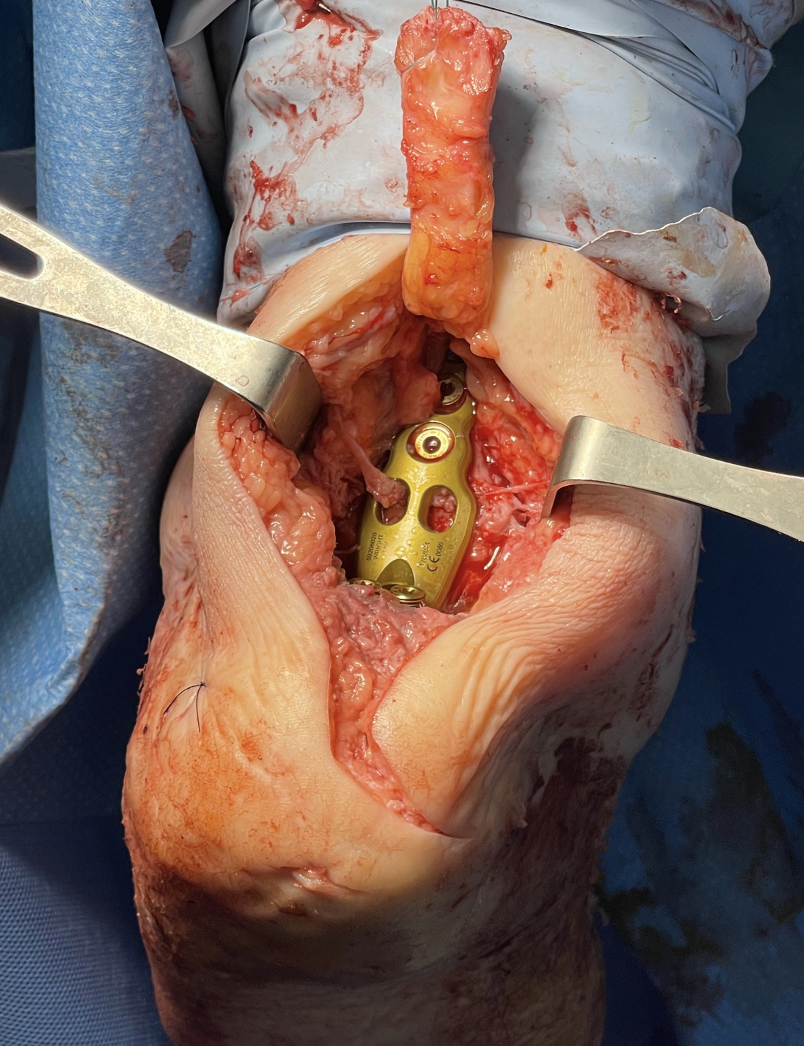

After removing the frame, we performed a revision in that same surgical session. We utilized a posterior Gaille approach due to an uncompromised soft tissue conduit. Reflecting the Achilles tendon superiorly, we used an acetabular reamer to create space for the femoral head allograft. This allowed the removal of the soft tissue occupying the distracted joint space. A fresh frozen femoral head allograft underwent injection with bone marrow aspirate and contouring to fill the tibiocalcaneal void. We then utilized Augment Regenerative Solutions (Stryker/Wright Medical) at the contact points between the allograft and tibiocalcaneal surfaces (see third photo to left). A posterior anatomic locking plate and a 6.5mm headless positioning screw secured the graft (see fourth photo to left). A lateral radiograph exhibited excellent restoration of height (see fifth photo to left).